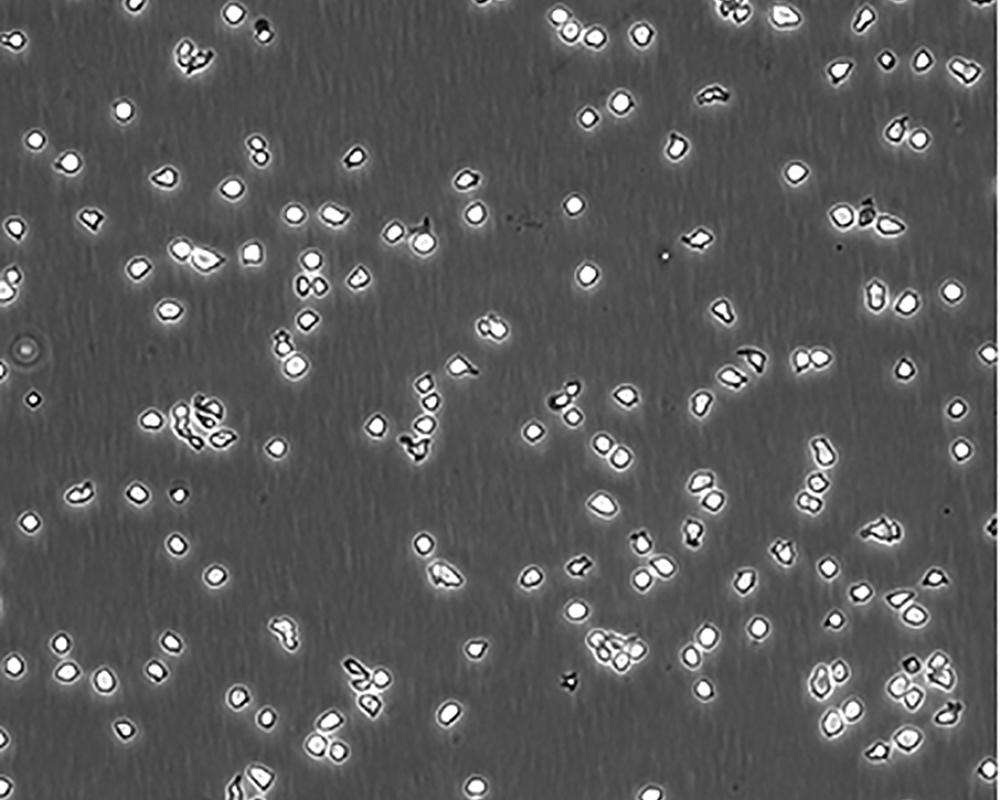

中文名稱 人Burkitt's淋巴瘤細胞

生長特性 suspension

形態(tài)特征 lymphoblast

細胞描述 R該細胞源自Burkitt's淋巴瘤患者的B淋巴細胞,EBNA、Fc陰性。